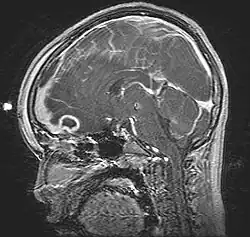

Guz Potta (ang. Pott's puffy tumor) – ciastowaty obrzęk skóry i tkanek miękkich okolicy czołowej, spowodowany zapaleniem szpiku kości czołowej, szerzącym się w kierunku czołowym bezpośrednio i drogą naczyń krwionośnych. Chełbotanie w miejscu obrzęku świadczy o obecności ropnia podokostnowego. Zakażenie może się też szerzyć w kierunku jamy czaszki, powodując ropień mózgu. Najczęstszą przyczyną jest zapalenie zatok czołowych, rzadziej uraz lub przyczyny jatrogenne, np. kraniotomia. Leczenie polega na drenażu chirurgicznym i długotrwałej antybiotykoterapii.